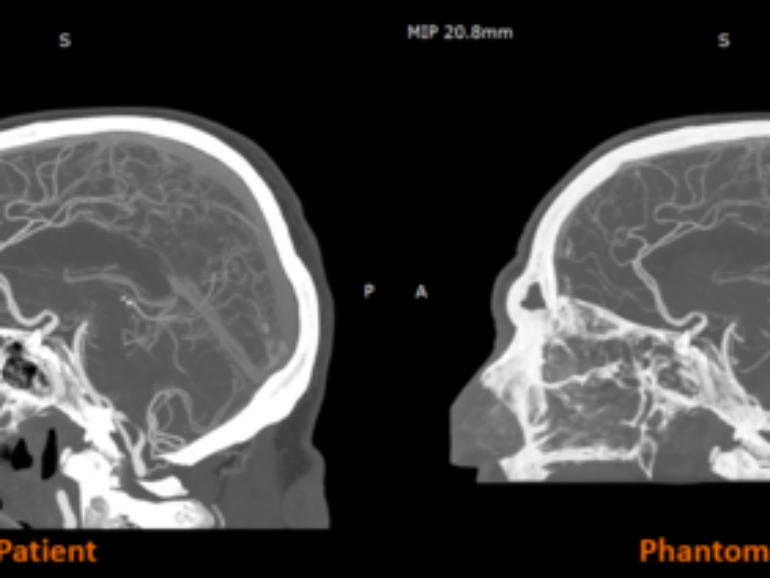

RadioMatrix: Stratasys Expands Access to Patient-Specific Radiopaque 3D Printing for Medical Imaging

3D printer OEM Stratasys has announced that its RadioMatrix radiopaque 3D printing material is now fully commercially available in the United States. Previously deployed in limited settings, the material can now be widely used by healthcare providers, medical device manufacturers, and research institutions for advanced medical imaging, education, and training purposes.